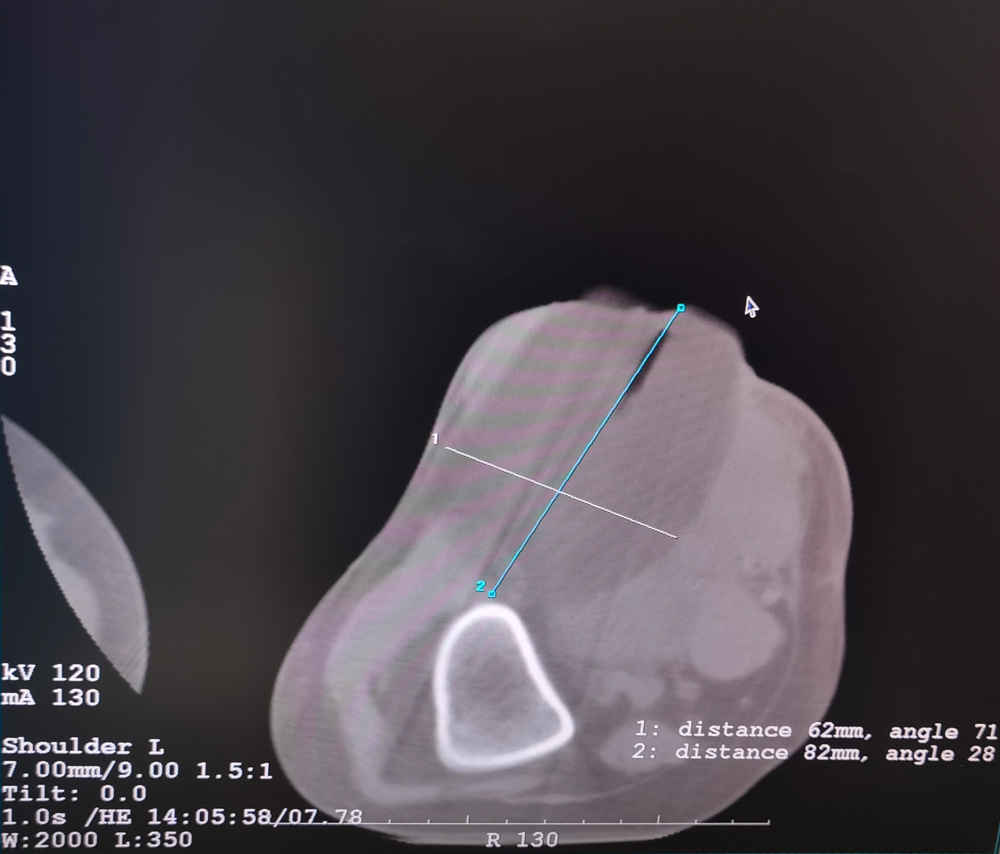

女,42歲,復(fù)發(fā)性脂肪瘤,病灶位于右側(cè)膝關(guān)節(jié),直徑大小13cm。采用雙針?lè)桨福策M(jìn)行6個(gè)凍融循環(huán),最大冰球直徑達(dá)8.2cm,術(shù)中多方位治療全面覆蓋病灶范圍。患者術(shù)后狀況良好。